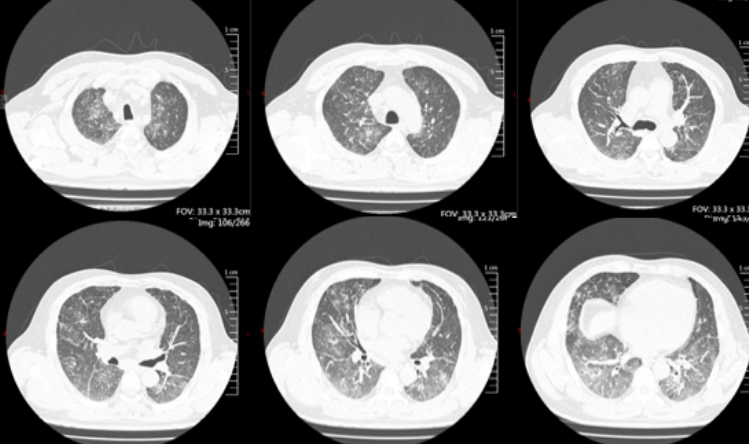

患者男性,55岁,因“气管切开术后2个月,呼吸困难10天”入院。CT检查提示气管环形狭窄(图1),最窄处仅1.53 mm,狭窄周围伴肉芽组织增生。

图片

1  患者CT检查